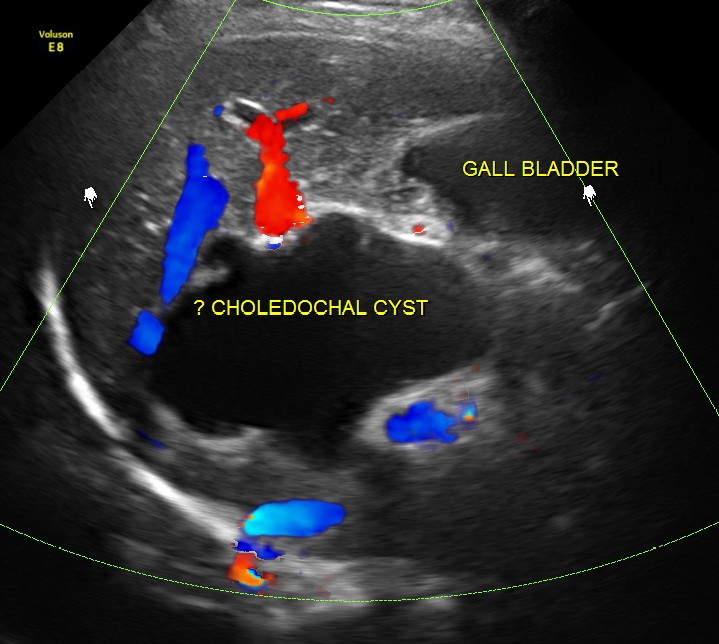

Prominent irregular cysts were seen in both the lobes of the liver ; the cysts were seen to arise from the biliary tract.

The diagnosis offered was Cholelithiasis , Choledochal cysts Type IV A and incidental bi cornuate uterus.

This patient was further evaluated with MRI , which confirmed the ultrasound findings . She underwent surgery successfully.